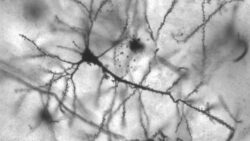

脳の体積と知能の高さは正比例する←わかる 男は女より脳の体積が1割ほど大きい←わかる

1: あけおめ@吉 23/01/03(火) 19:35:27 ID:MWSU 男と女に知能の差はない←??? ゲームのゾワっとする演出挙げてけ